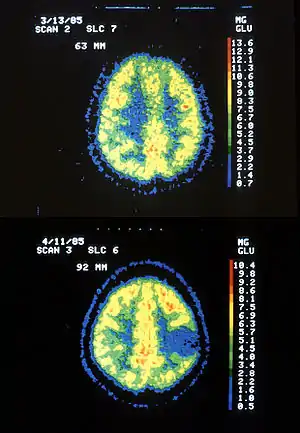

| Two PET images — the upper of which shows a normal brain and the lower shows astrocytoma. | |